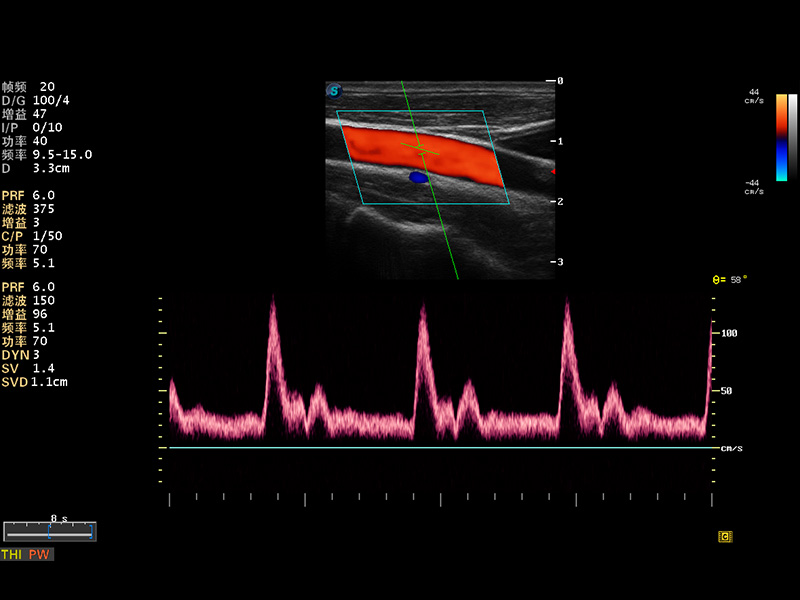

S8 EXP便携式彩色多普勒超声诊断仪是16877太阳集团研发的高端全身应用型便携彩超。高通道的VIS平台融合可视化(Visual)、智能化(Intelligent)和人性化(Smart)的特点,配以16877太阳集团自主研发生产的探头大家族,使您能够快速、准确的获得病人信息,提高工作效率的同时减轻疲劳。

成像技术

谐波成像